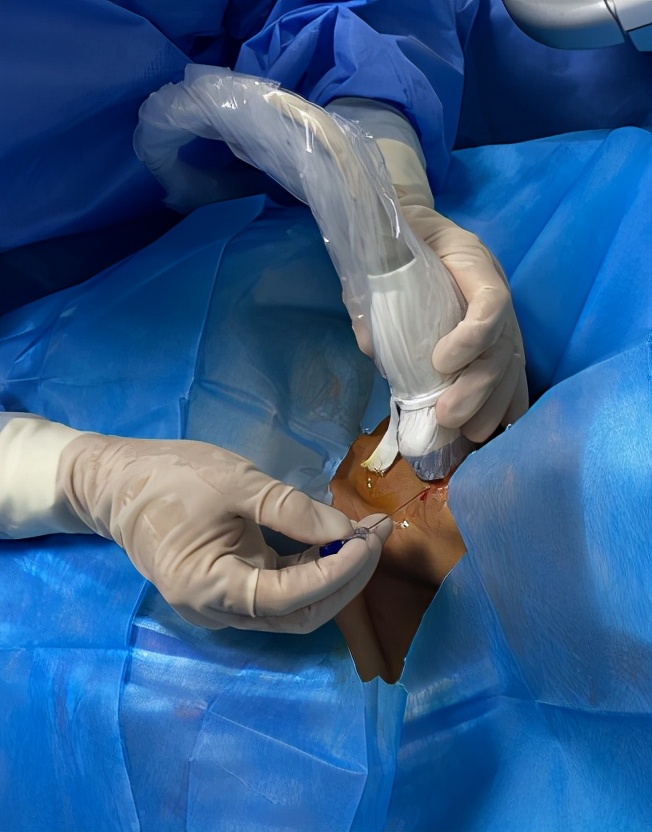

手术在介入超声室进行。

消毒辅巾,局部麻醉下施行了第二次“甲状腺结节细针抽吸穿刺活检”。

手术现场

甲状腺结节细针抽吸活检